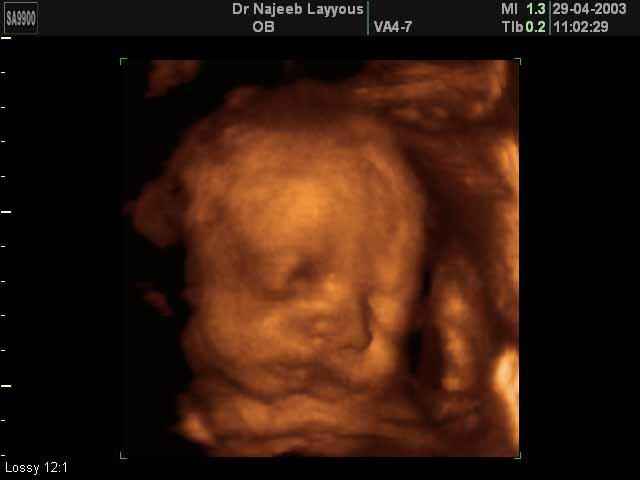

- Fetal Face Ultrasound Photos

3D Fetal Face Ultrasound Scan Photos | Dr N Layyous